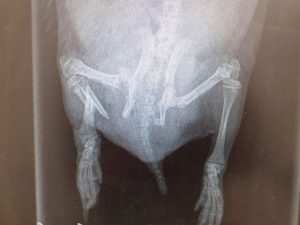

We had a hog brought in to us the other day after it was seen on a wildlife camera dragging one of its hind legs. He had a healed wound